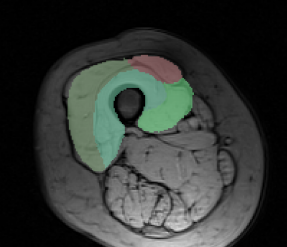

Dataset. The dataset consists of 30 MRI volumes of the thigh region of dimensions . The various segments correspond to 4 different muscle groups together with the background class. We randomly split the dataset into 80% for training and 20% for testing. In order to reduce the training time for both our method and the baselines, we divide each volume into volumes of dimension .

Results. Fig. 1 shows the test loss for three different methods: (i) the initial hand-tuned parameters ; (ii) the baseline structured SVM with distance transforms; and (iii) our proposed approach using latent SVM. As can be seen from Fig. 1, latent SVM provides significantly better results than the baselines—even when using the distance transform. For the 4 x 5 hyperparameter settings that we report (that is, four different values of and 5 different values of ), latent SVM is significantly better than SVM in 15 cases, and significantly worse in only 2 cases. Note that latent SVM provides the best results for very small values of , which indicates that the upper bound on the empirical risk in tight. As expected, for sufficiently large values of , all the methods provide similar results. For the best settings of the corresponding hyperparameters, the percentage of incorrectly labeled voxels as follows: (i) for , ; (ii) for structured SVM, ; and (iii) for latent SVM, . Fig. 2 shows some example segmentations for the various methods.